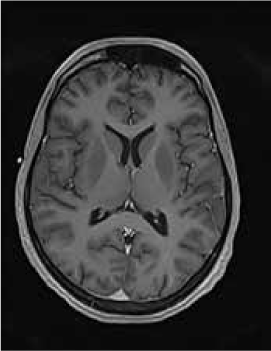

Magnetic resonance imaging (MRI) of the brain showed symmetrically increased T2-weighted and fluid-attenuated inversion recovery signal in the central pons (Figure 1) and in the striatum of the basal ganglia (Figure 2), with no contrast enhancement seen on corresponding T1-weighted postgadolinium images (Figures 3 and 4). Spinal MRI (Figure 5) demonstrated high signal on T2-weighted images from the area postrema in the medulla extending caudally to the T9 thoracic segment, with marked cord swelling and mild enhancement on T1-weighted postcontrast studies (Figure 6), in keeping with a longitudinally extensive inflammatory myelitis.

Postcontrast magnetic resonance image of brain show nonenhancing changes in pons

Postcontrast magnetic resonance image of brain show nonenhancing changes in basal ganglia

The clinical and radiologic features supported the diagnosis of NMO. However, the symmetrical pontine and basal ganglia high signal without contrast enhancement were considered to be strongly suggestive of concomitant ODS (pontine and extrapontine myelinolysis).